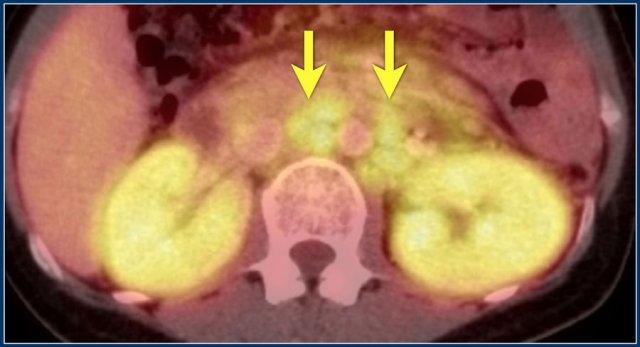

PET-CT cho thấy tổn thương thận lan tỏa và các hạch bạch huyết cạnh động mạch chủ dương tính (mũi tên).